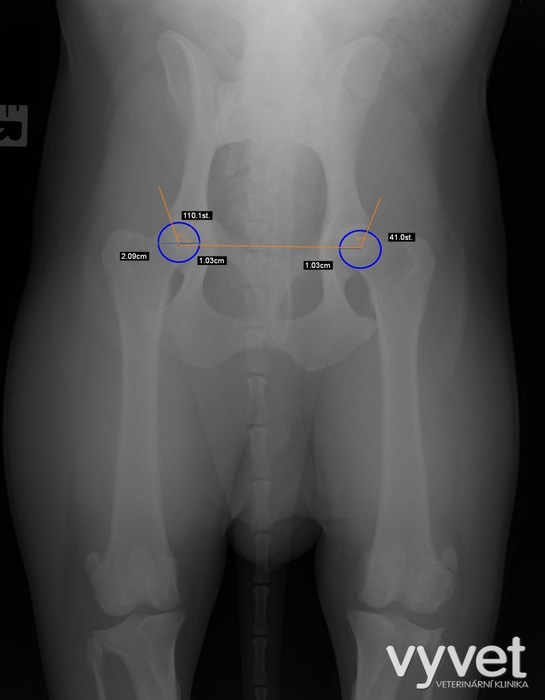

V tomto případě se jedná o šestiletou kříženku psa. cca 20kg

Utekla majiteli a byla doslova přejeta zadními koly auta. Při autoúrazu utrpěla mnohočetné zlomeniny mimo jiné i hrudní končetiny. viz obr.

Nejzávažnější fraktury byly v oblasti kyčelního kloub. Obě kyčelní jamky byli rozlomené.

Bez chirurgického zásahu se jednalo o stav neslučitelný se životem.